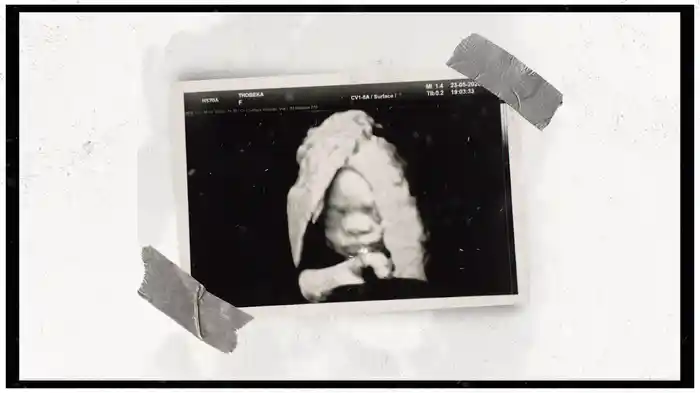

Nokuthula (Visualizer)